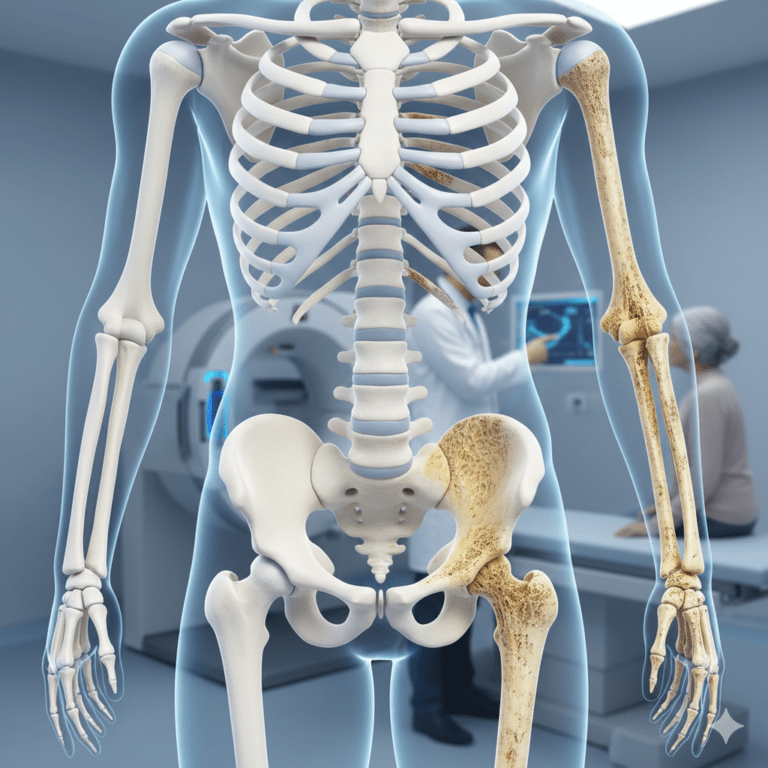

فهم المرض، أسبابه، أعراضه، طرق العلاج وأهم النصائح للوقاية والتعافي مقدمة: حقيقة العظام الحية يظن الكثيرون أن العظام مجرد دعائم صلبة في الجسم، لكن في الواقع هي أنسجة نابضة بالحياة تعتمد على تدفق دم مستمر لتبقى قوية وسليمة. عندما ينقطع…

تعد هشاشة العظام (Osteoporosis) واحدة من أكثر الحالات الطبية انتشاراً بين كبار السن، وتُلقب بـ “اللص الصامت” لأنها تضعف كتلة العظام تدريجياً دون ألم واضح، حتى يفاجأ المريض بكسر ناتج عن سقطة بسيطة. يوضح لنا الأستاذ الدكتور أحمد سلام، استشاري…